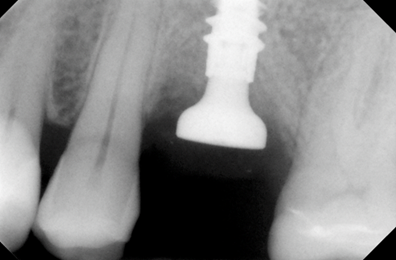

Этот пациент обратился ко мне с жалобами на сильную боль, покраснение и отек вокруг только что установленной коронки на имплантате. В анамнезе было следующее: был снят аналоговый оттиск с уровня имплантата и отправлен в лабораторию для изготовления коронки. У лаборанта не было указаний относительно расположения шейки имплантата по отношению к мягким тканям и кости.

Была выбрана самая короткая высота десневой манжеты (GH), так как она является наиболее безопасной с эстетической точки зрения, поскольку металлическая кромка не будет видна над десной. При доставке коронки на имплантат стоматолог столкнулся с трудностями при «посадке» коронки на абатмент.

Коронка была установлена со значительным сопротивлением для достижения необходимого значения торка. Ущемление твердых и мягких тканей из-за очень острого профиля выступа вызывает давление на кость, что приводит к некрозу и, в конечном итоге, к потере маргинальной кости в этой области. Чтобы избежать подобных осложнений, необходимо выбирать правильный абатмент.

На основе ОПТГ, сделанного после установки или имплантата (рис. 2), стоматолог может выбрать подходящую высоту десневой манжеты для абатмента и направить техника, предоставив рентгеновский снимок и/или спецификацию формирователя десны. Большинство систем имплантатов имеют синхронизированные формы и контуры хирургических абатментов и компонентов протеза.